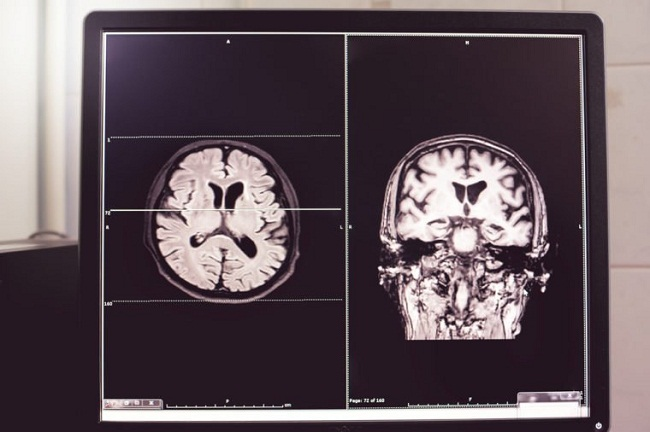

پس از بررسی بافت مغز، محققان مشاهده کردند موش هایی که به طور متناوب LPS به آنها تزریق می شد، تغییراتی را در هیپوکامپ نشان دادند. هیپوکامپ نقش کلیدی در حافظه و یادگیری دارد و یکی از مناطق مغز است که اولین نشانههای تباهی را در بیماری آلزایمر نشان میدهد.

این تغییرات شامل افزایش بیان ژن سیتوکین اینترلوکین -6 (IL-6) در هیپوکامپ موش های تحت درمان با LPS بود. این نتایج با مطالعات قبلی که نشان دهنده میزان بالای IL-6 در نواحی مغز مربوط به عملکرد شناختی، پس از تزریق LPS است، مطابقت دارد.

محققان همچنین دریافتند تجویز LPS انعطاف پذیری بین نورون ها را تعدیل می کند، اما انتقال سیگنال پایه را تغییر نمی دهد. به ویژه موشهایی که LPS دریافت کردند، کاهش تثبیت سیناپسی بین نورونها در هیپوکامپ نشان دادند.

تثبیت سیناپسی (LTP) تقویت سیناپس ها بین نورون ها پس از فعال شدن مکرر یک نورون توسط نورون دیگر است. این تقویت اتصالات بین نورون ها باعث می شود نورون توسط نورون متصل به آن آسان تر فعال شود. کاهش تثبیت سیناپسی در نورون های هیپوکامپ موش های تحت درمان با LPS به ویژه با توجه به این که تثبیت سیناپسی مکانیسم اساسی شکل گیری خاطرات و یادگیری است، قابل توجه است.

این نتایج نشان میدهد التهاب مکرر ناشی از تزریق LPS در موشهای میانسال میتواند به نقص شناختی همراه با تغییرات در هیپوکامپ بینجامد.